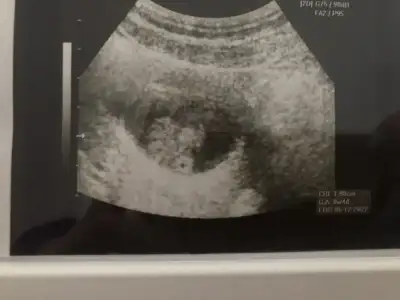

10 hafta karindan tahmin edermisin canim

Eklentiler

• IMG_20220502_150812.webp

IMG_20220502_150812.webp

19,9 KB · Görüntüleme: 81